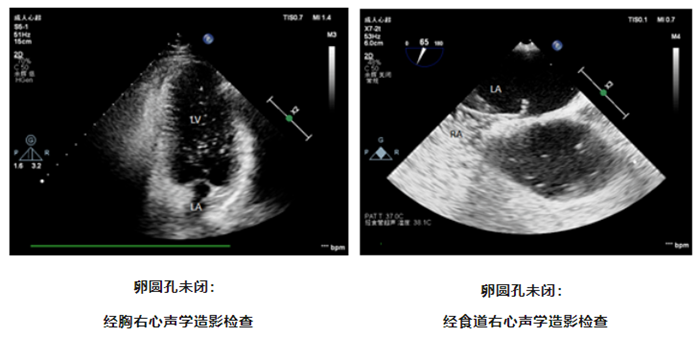

怎样发现卵圆孔未闭

超声心动图是卵圆孔未闭的首选检查,包括经胸超声心动图及经食道超声心动图,都能够评价房间隔解剖结构和分流情况。经胸超声心动图扫查需要透过皮肤、皮下肌肉及脂肪组织对房间隔的分流进行评估,成人受各种因素如肥胖、肺气过多等影响,很难准确诊断及测量 PFO,检查结果可能为假阴性。而经食道超声心动图可清楚观察房间隔解剖结构,是诊断 PFO 的金标准。而超声心动图结合右心声学造影并配合规范的激发试验检查, PFO 的检出率可明显提高。

什么是右心声学造影

右心声学造影,又称为振荡生理盐水增强显影,目前常用振荡的无菌生理盐水或糖盐水配制声学造影剂,由于其产生的微泡较大,不能通过肺循环,只能在右心显影,故称为右心声学造影剂,从而可应用于判断是否存在心内分流和肺内分流。